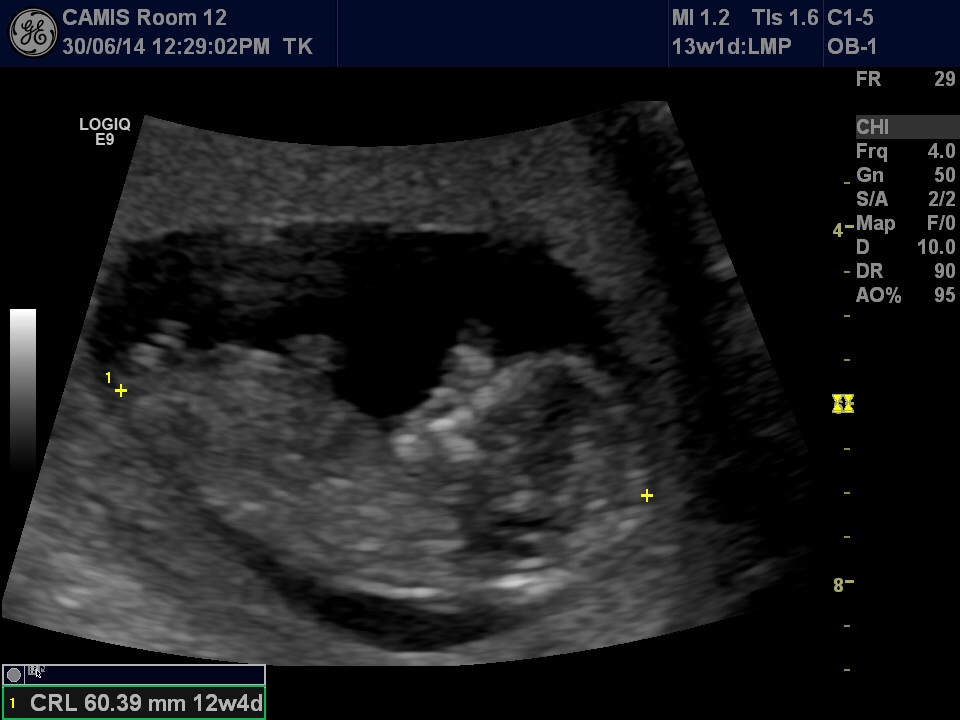

On another forum a lady said it looked like a boy nub but I see a horizontal line. As for skull theory my son had a very girl looking skull (very rounded) and this one is totally different!!